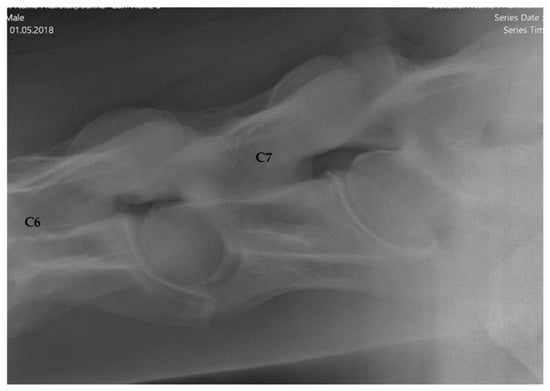

2.1.2. Radiographic Assessment

- Group 1 = normal: no periarticular new bone formation at ventral margins of APJ, intervertebral foramina clearly visible.

- Group 2 = mild APM: minimal/equivocal enlargement and sclerosis of APJ with mild osteophytosis ventrally, intervertebral foramina open/slightly obscured by new bone formation.

- Group 3 = moderate/severe APM: clear enlargement and sclerosis of APJ with moderate osteophytosis ventrally, significant reduction/loss of intervertebral foramina.